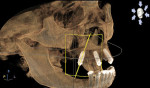

3D dentistry is truly transformative. By integrating computer-assisted implantology via GALILEOS® CBCT imaging (Dentsply Sirona Imaging, dentsplysirona.com) clinicians can confidently offer streamlined solutions for complex dental problems and provide advanced treatment options. Dentsply Sirona’s innovative SmartFix® concept affords implant dentists unique, reliable rehabilitation possibilities. The Astra Tech EV drilling protocol ensures primary stability for implant placement when immediately loading. Use of a digital workflow to diagnose and treatment plan removes guesswork, provides predictability, and ensures precision to return esthetics and function. The Profile EV implant, designed to follow the geometry of the alveolar ridge, decreases the need for bone reduction when tilting posterior fixtures by placing them at or slightly below the crestal bone. Restorative product options provide expanded choices with regard to angulations, tissue depths, and interocclusal spaces. Available prosthetic products simplify the restorative process for converting an immediate denture to an implant-retained fixed provisional prosthesis during the “teeth in a day” treatment procedure. As shown in this case, the patient gains expeditious improvement in esthetics, speech, and function with a single-staged, immediate-load, fixed hybrid prosthetic solution.

The Profile EV implant is designed to minimize marginal bone remodeling and improve crestal bone preservation, lessening the need for bone augmentation or reduction and enhancing postoperative healing.

Combining the Profile EV implant with planning software and using surgical guide safeguards enables precise placements with improved control of depth, angulation, and timing. The SmartFix concept streamlines all-on-4 oral rehabilitation.